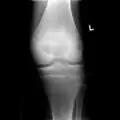

A variety of imaging studies can be used to diagnose chondroblastoma, with radiographs being the most common.[10][8] Laboratory studies are not considered useful.[14] Classical chondroblastoma (appearing on long bones) appears as a well-defined eccentric oval or round lytic lesion that usually involves the adjacent bone cortex without periosteal reaction.[10][13] A sclerotic margin can be seen in some cases.[10][13] For long bone chondroblastomas the tumor is typically contained to the epiphysis or apophysis but may extend through the epiphyseal plate.[10][13] Chondroblastomas are usually located in the medullary portion of bones and can, in some cases, include the metaphysis.[10][13] However, true metaphyseal chondroblastomas are rare and are typically the result of an extension from a neighboring epiphyseal legion.[10][13] Most lesions are less than 4 cm.[10] A mottled appearance on the radiograph is not atypical and indicates areas of calcification which is commonly associated with skeletally immature patients.[10] Additionally, one-third of all cases involve aneurysmal bone cysts which are thought to be the result of stress, trauma or hemorrhage.[10] In cases involving older patients or flat bones, typical radiographic presentation is not as common and may mimic aggressive processes.[10][13]

1. a. X-ray of chondroblastoma of thigh bone near knee